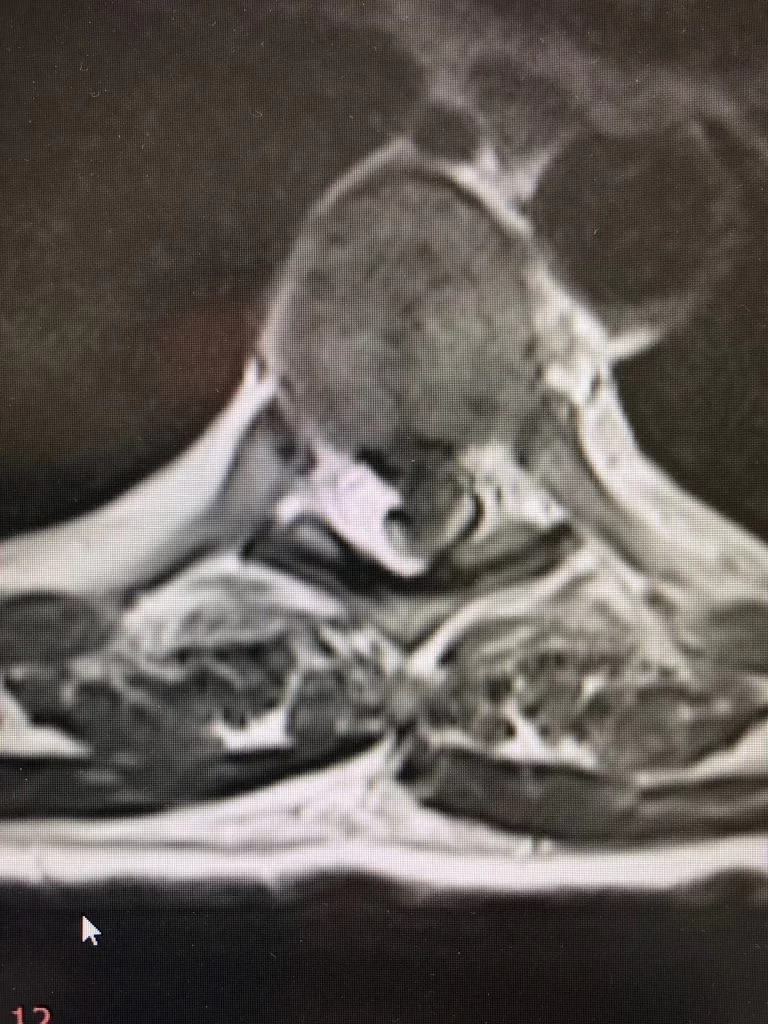

Ο απεικονιστικός έλεγχος ανέδειξε δύο επασβεστωμένες θωρακικές δισκοκήλες στο ύψος Θ6/7 και Θ7/8.